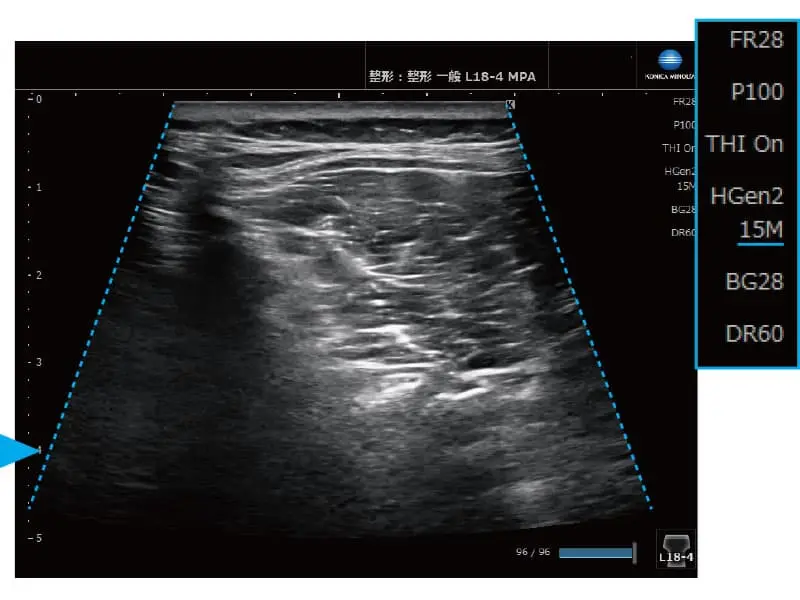

簡単操作で画像を最適化

MPA® 機能(Multi Parameter Adjuster)

表示深度を変更するだけで、あらかじめ設定した画質パラメーターが適用されます。例えば、表示深度を浅くすると高周波に、深くすると低周波や台形走査へ自動的に切り替わります。

≪深度:浅い≫ 台形走査OFF

≪深度:深い≫ 台形走査ON